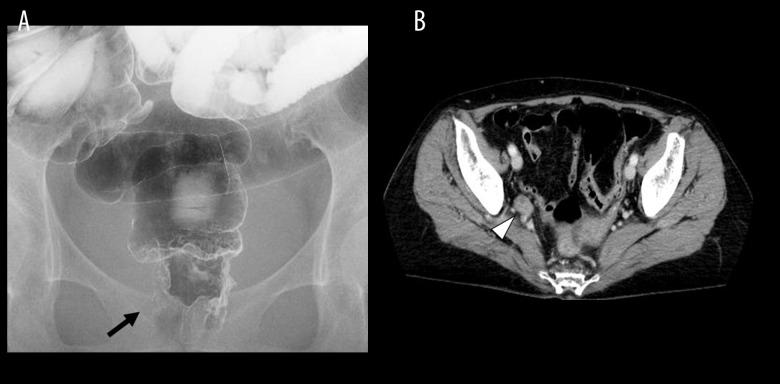

BACKGROUND This report describes the case of a 73-year-old woman treated for rheumatoid arthritis with lower rectal carcinoma who underwent abdominoperineal resection, lateral regional lymph node resection, and partial hepatectomy by hand-assisted laparoscopic surgery (HALS). More recently, HALS has proven to be useful in multiple organ resections. CASE REPORT A 73-year-old woman who presented with hematochezia was diagnosed with lower rectal cancer and referred to our hospital. The patient had a history of rheumatoid arthritis and was taking oral nonsteroidal anti-inflammatory drugs. After further evaluation, the patient was diagnosed with stage IV rectal cancer with a metastatic liver lesion and a right lateral lymph node metastasis. All lesions were resected using HALS. A 50-mm longitudinal umbilical incision was created for use as a hand access site, and 3 ports with a diameter of 5 mm each were inserted into the lower abdomen to perform right lateral lymph node dissection and abdominoperineal resection. HALS was performed in the upper abdomen, where the liver was used to partially resect segment S6. The patient was discharged without complications 13 days after the operation. CONCLUSIONS In this complex case of advanced rectal carcinoma with liver metastases, use of the HALS surgical method was shown to be possible. Immunomodulatory treatment for rheumatoid arthritis may have influenced the outcome for this patient.

病例报告 一位 73 岁女性因血便就诊,被诊断为低位直肠癌并转至我院。该患者有类风湿关节炎病史,正在口服非甾体抗炎药。进一步评估后,该患者被诊断为 IV 期直肠癌,伴有肝转移病灶和右侧侧方淋巴结转移。所有病灶均采用 HALS 切除。脐部做一长 50mm 的纵向切口作为手进入部位,在下腹插入 3 个 5mm 直径的端口,进行右侧侧方淋巴结清扫和腹会阴直肠切除术。HALS 在上腹部进行,利用肝脏部分切除 S6 段。术后 13 天患者无并发症出院。